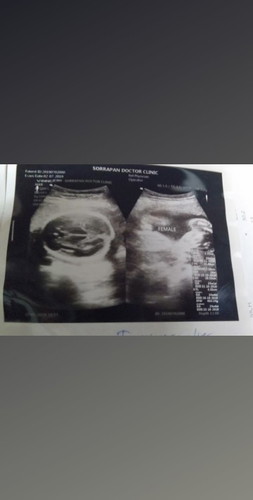

อยากรู้คุณแม่ดูกันยังไงค่ะ น้องเพศอะไรค่ะดูให้ทีค่ะใครดูออก อยากรู้ว่ารูปด้านซ้ายนี้คือหน้าน้องหันมาหาเราใข่มัยค่ะ

ซ้ายมือคือกระโหลกศรีษะ Femaleคือเพศหญิงค่ะ